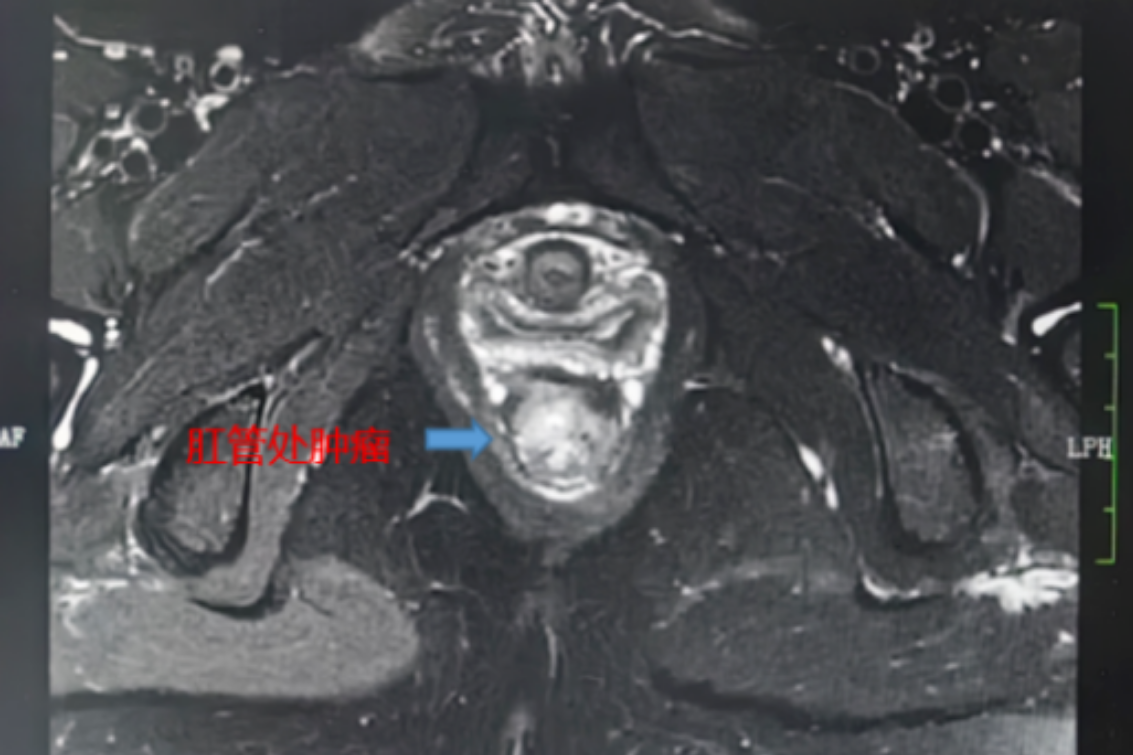

精准放疗,守护“底线”——一位肛管癌患者的保肛之路